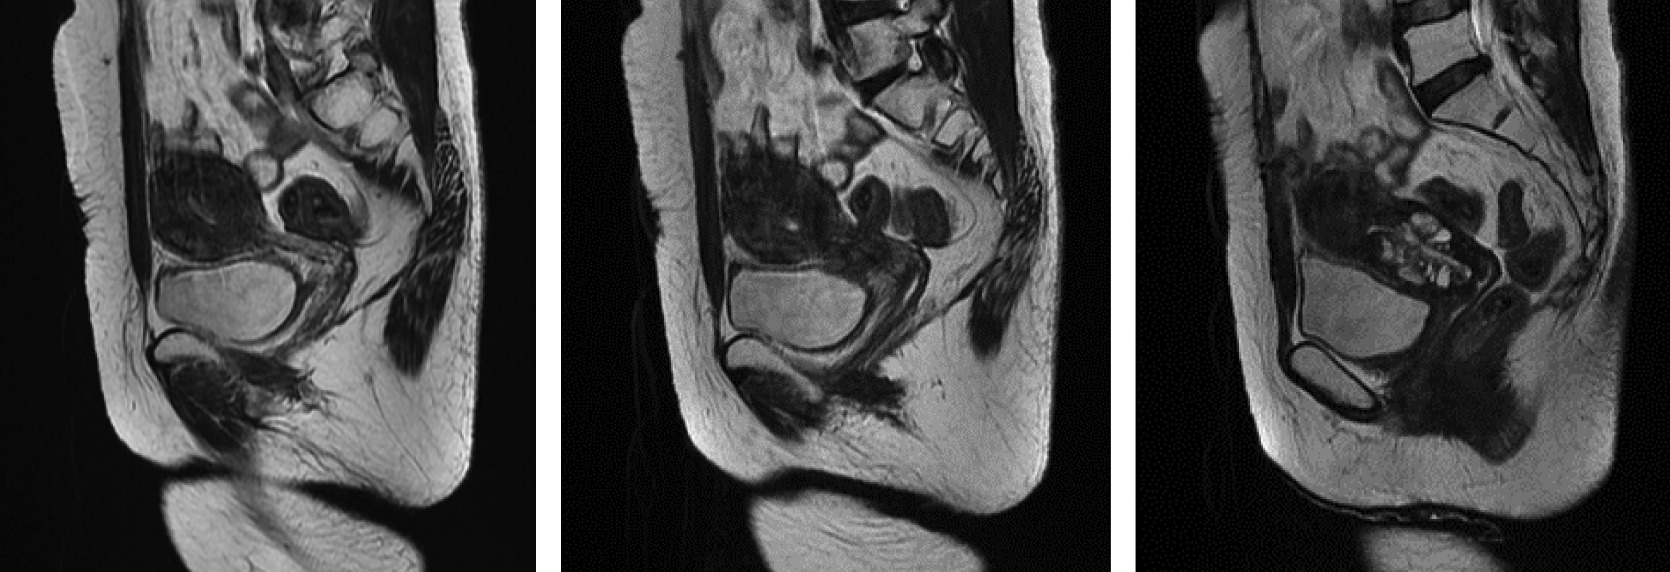

YANG Jia-xin, E-mail: WANG Yao, YANG Jia-xin. Glassy Cell Cervical Carcinoma:A Case Report and Literature Review[J]. Journal of International Obstetrics and Gynecology, 2023, 50(2): 228-233.